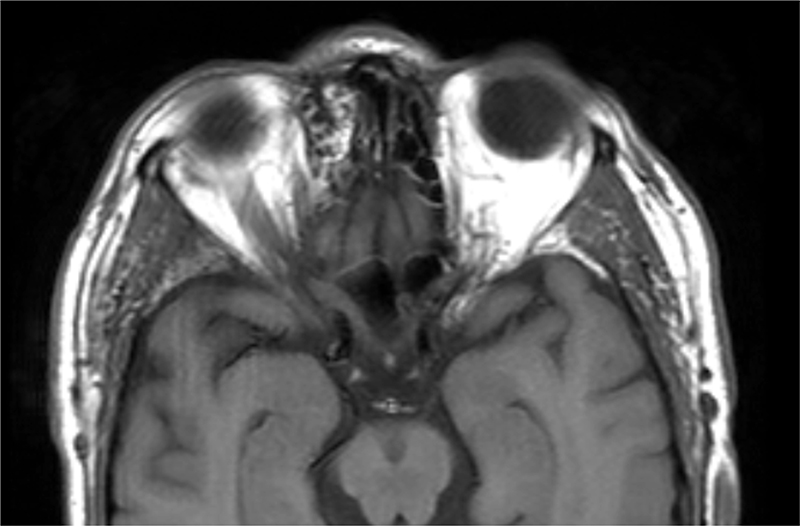

Figura 3b. RM T1 axial con contraste. La musculatura extrínseca ocular de la región (oblicuo superior) queda incluida en las alteraciones óseas lo que condiciona una restricción del la polea y el cuadro de síndrome de Brown adquirido.